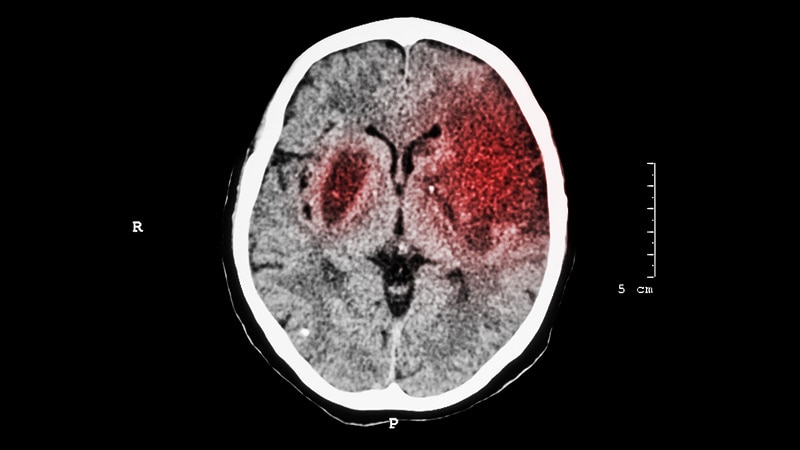

Neurology

- Neurology